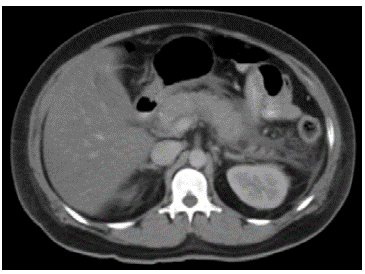

A 30-year-old patient was admitted due to a two-day history of epigastric pain radiating to the sternal and precordial region and 10 food vomiting episodes; he denied having a fever. On admission to the emergency room he was dehydrated and tachycardic with a normal blood pressure. On physical exam he had no pain on abdominal palpation and his neurological exam was within normal limits. His glucose level on admission was 352 mg/dL, and blood gases revealed partially compensated metabolic acidosis without impaired oxygenation (ph 7.25, HCO314, PaCO229, PaO263, BE -10). Laboratory tests showed a complete blood count within normal limits, amylase 648 U/L, hyponatremia at 120 mmol/dL (corrected for glucose level: 124 mmol/dL) and 14.10% glycosylated hemoglobin. Management was begun with crystalloids in the context of diabetic ketoacidosis (new-onset diabetes), implementing crystalloid resuscitation and initiating insulin infusion therapy. He was also diagnosed with Marshall 2, APACHE II 10 pancreatitis. Hepatobiliary ultrasound ruled out pancreatic lithiasis, and triglycerides were ordered since he did not have a history of alcohol consumption. The triglyceride results were 6,700 mg/dL with total cholesterol of 1,071 mg/ dL. Plasmapheresis was not available, therefore a bolus of 80 units/kg of unfractionated heparin was added to the insulin treatment and was continued at 18 U/kg/hour. Abdominal tomography was compatible with Balthazar B (Figure 1). The metabolic acidosis was corrected, and adequate glucose control was achieved. Dextrose, insulin and heparin infusions were continued, with the heparin maintaining a PTT 2.5 times the institution's reference value. The patient showed clinical improvement of the abdominal pain and daily follow up of the triglycerides showed a significant decrease. The patient tolerated oral ingestion, and fenofibrate was begun as complementary treatment. The infusion treatment was maintained for four days, his triglycerides were below 500 mg/dL on the fifth day, and he was transferred to the regular floor without complications (Table 1).